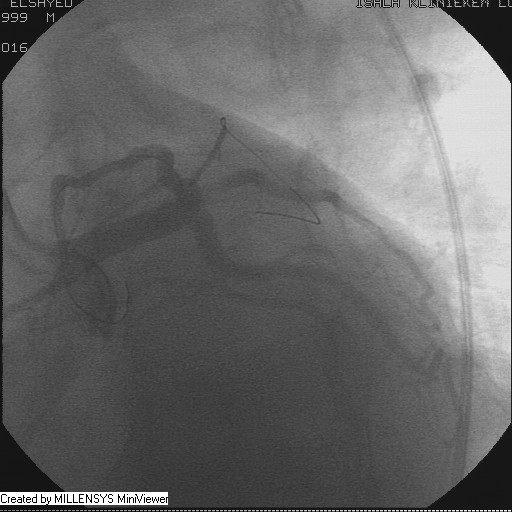

Patient transfered to Cardiac Catheterization Laboratory, coronary angiography showed atherosclerotic coronaries but without significant lesions, especially LAD that was patent with TIMI 3 flow (Figure 1- 5). Re-evaluation of the Angiography showed a small stump that can be for an occluded 1st diagonal (Figure 2a), at that level the LAD has a non-significant lesion.

Figure 1A

Figure 1